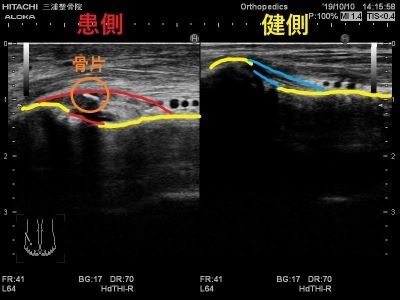

またここの損傷では

レントゲンには中々写りづらい

骨折が隠れていることも多いです。

エコーの良い所として

動かしながらも観れるので

関節がどのくらいぐらついているかなども

判断できます。

こういった画像で状態や動きも参考にしながら